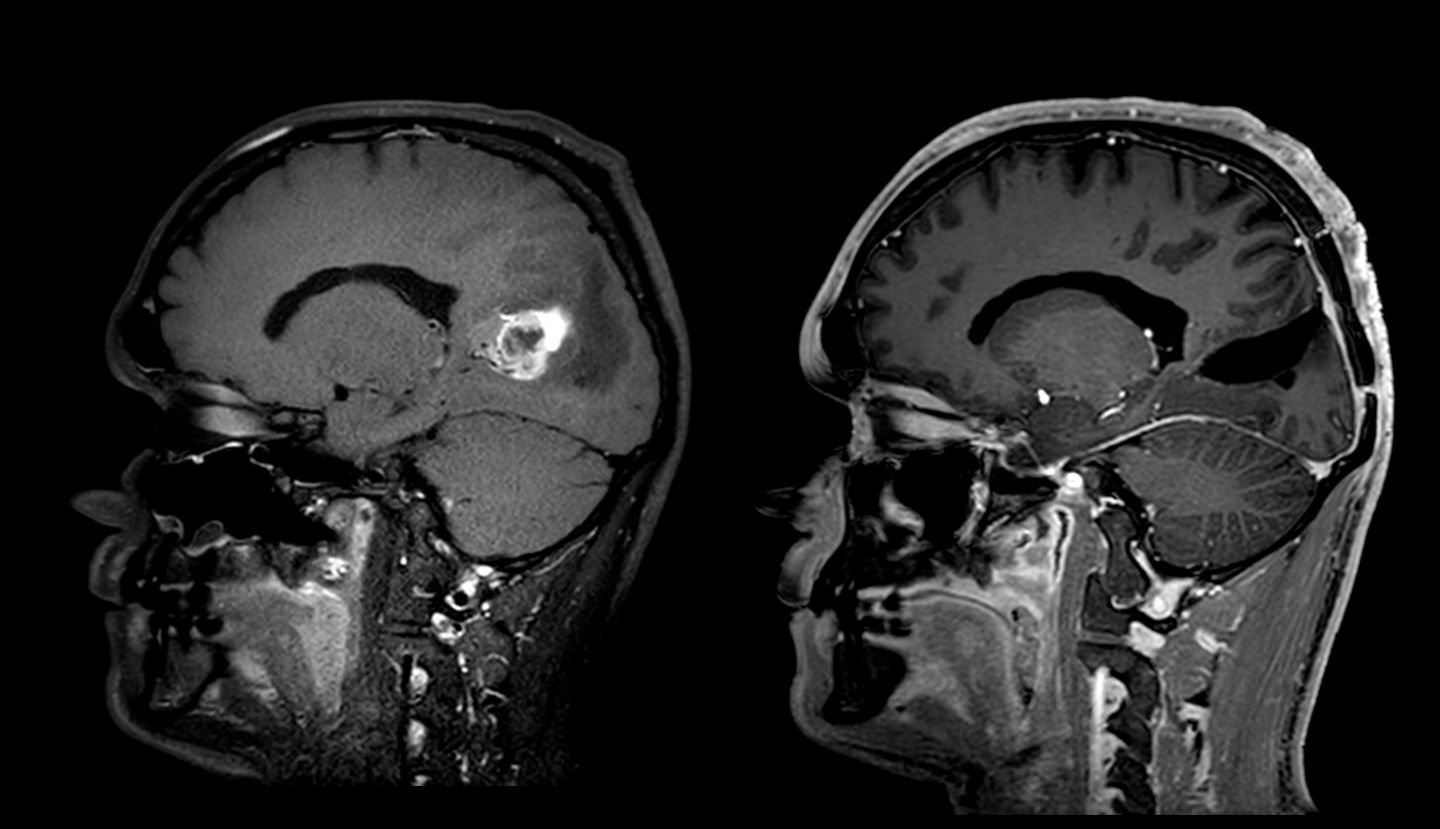

Glioblastom vor Operation (links) und nach Entfernung (rechts).